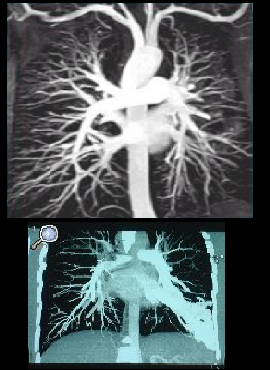

Arteriografía

(vasodilatación/fistulaAV LII)